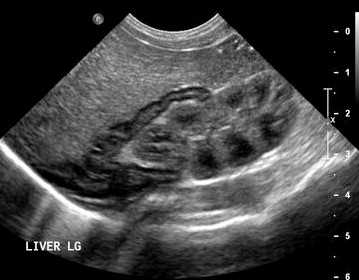

На УЗИ тимус гипоэхогенный в сравнении с щитовидной железой, и изоэхогенный миакарду. Контур тимуса четкий; ровный по передней поверхности, но волнистый сзади. У детей младшего возраста эхо-структура железы однородная мелкозернистая, а у старших детей и взрослых точечные гипо- и гиперэхогенные сигналы перемежают — это смесь жира и лимфоидной ткани. Внутри тимуса можно разглядеть тонкие гиперэхогенные фиброзные перегородки, которые делят железу на отсеки. Из-за фиброзной капсулы края тимуса хорошо контурируют. Расположение, форма и размер тимуса сильно варьируют.

| Фото. Поперечный срез тимуса новорожденного, ребенка старшего возраста и взрослого. | ||

| Фото. А — Поперечный срез тимуса у новорожденного. Б — У детей раннего возраста, особенно при крике, верхняя часть тимуса может подниматься на шею через яремную вырезку, тогда он определяется позади щитовидной железы (звездочка). В — На саггитальном срезе хорошо видно, что тимус (эктопическая долька на шее) гипоэхогенный по сравнению с щитовидной железой. | ||